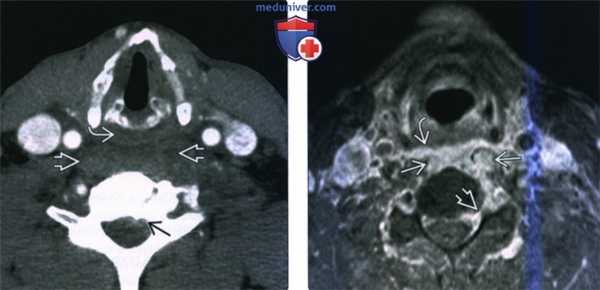

(Слева) КТ с КУ, пациент с септицемией, аксиальная проекция. В анамнезе имеются сведения об употреблении наркотических препаратов. Основной жалобой является интенсивная боль в шее. Имеется выраженное утолщение предпозвоночных тканей со смещением гортаноглотки кпереди. Имеются признаки эпидуральной флегмоны.

(Справа) MPT Т1ВИ FS с КУ, аксиальная проекция, этот же пациент. Интенсивное накопление контраста в предпозвоночных мягких тканях с инфильтрацией длинных мышц шеи и заглоточного пространства. Слева имеются признаки поражение эпидурального пространства и межпозвоночного отверстия.

(Слева) МРТ Т1ВИ с КУ, аксиальная проекция. Однородное накопление контраста в предпозвоночных мышцах с увеличением их объема. Жировая клетчатка заглоточного пространства смещена кпереди. Имеются признаки аномального накопления контраста в эпидуральном пространстве, происходит формирование эпидурального абсцесса, окруженного кольцом накопления контраста.

(Справа) MPT STIR в сагиттальной проекции у пациента со спондилодисцитом С6-С7 позвонков. Отмечается сужение межпозвоночного пространства, аномально гиперинтенсивный сигнал от тел позвонков. Имеются признаки предпозвоноччной флегмоны и эпидурального абсцесса. Имеется выраженное сдавливание спинного мозга.